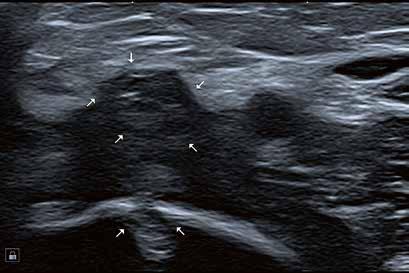

Hochauflösender Ultraschall in der Sportpraxis

Wie kamen Sie zur Sonographie?